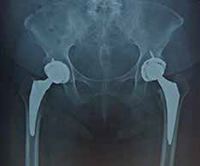

両脚の人工股関節置換後のレントゲン

股関節の変形が始まってくると、リハビリだけでは治まらなくなります。痛みのために、友人との旅行や買い物にも行きづらく、趣味のゴルフもだんだん遠のき、外出をしない引きこもり状態になっている人も見られます。進行期から末期の方には、手術療法を勧めています。この段階になると、関節の変形は止まりません。悪くなるいっぽうで決して改善しません。痛みが強く、歩くのも困難になってしまうかもしれません。そうなる前に、人工股関節置換術をしてはいかがですかと提案することもあります。